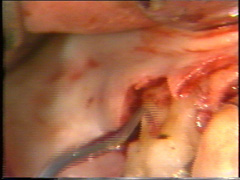

Visión palatina:

Eliminación del tejido de granulación.

El colgajo

se levanta teniendo cuidado de no desgarrarlo.